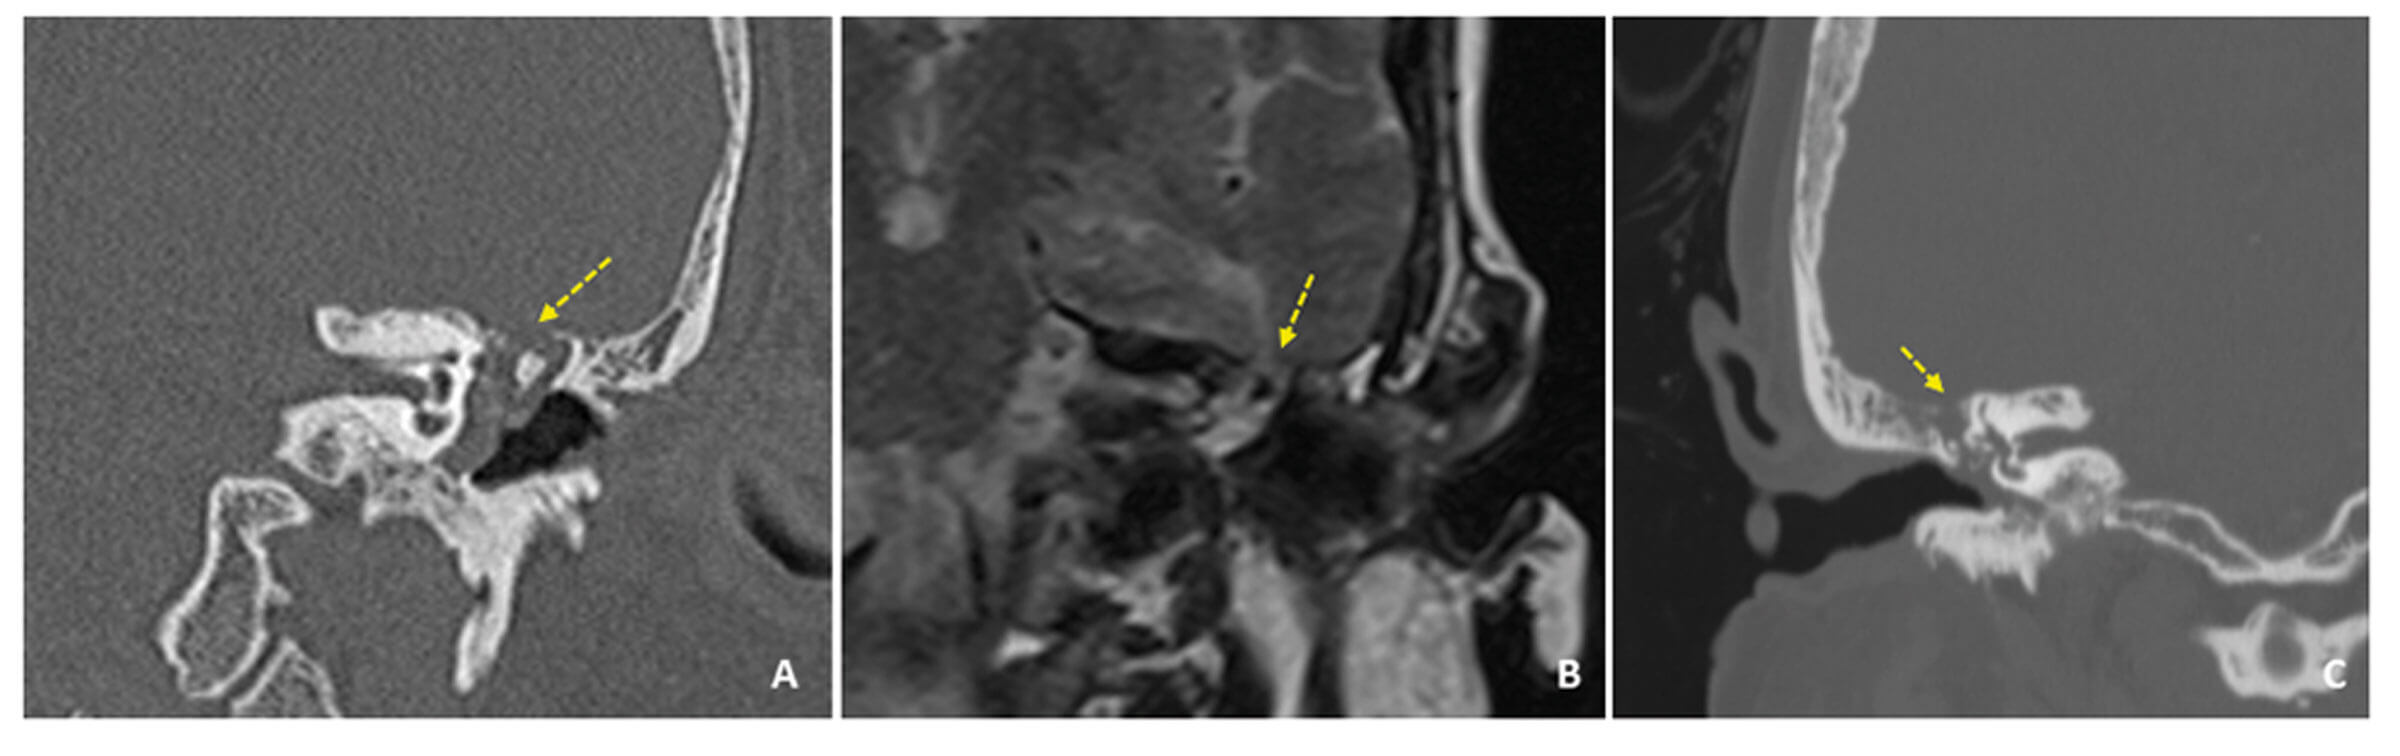

Figure 1. Examples of tegmen defects with meningoceles: left meningocele on coronal plane CT temporal bones (A); and on post-gadolinium T1-weighted coronal plane MRI (B); small defect on the right side in patient with CSF leak and recent meningitis on coronal plane CT temporal bones (C) (highlighted with arrows).

We advocate dual modality imaging of the temporal bone when a middle fossa defect is suspected; CT and MRI are essential in delineating the bony and soft tissue anatomy respectively (Figure 1).